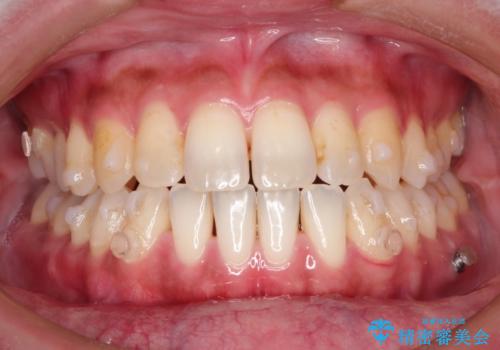

Invisalign インビザライン によるガタつき、受け口傾向の改善

奥歯の位置関係の修正は難儀することが多いマウスピース矯正ですが、割とスムーズに奥歯の位置関係の修正をすることができました。

クロスバイトもきれいになり、きれいな歯並びとなりました。